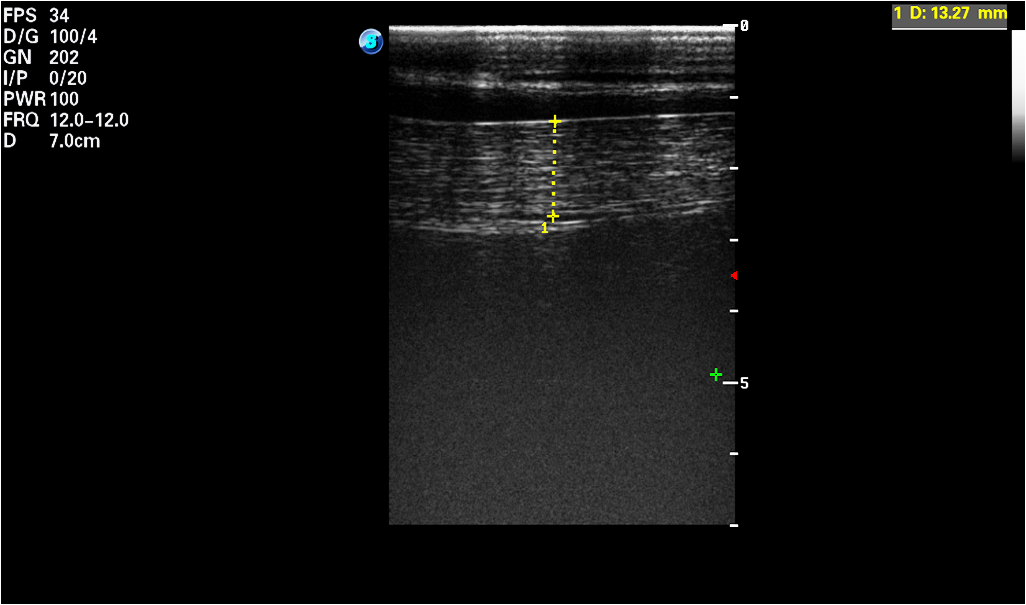

[ cap = Animal features, caption = Measured features (meanSD) of horses (H.1-H.16) and donkeys (D.1-D.16): the length of hair coat and the thickness of the subcutaneous fat plus skin (SF-Skin)., label = tab:animalsft, pos = h] lcc \tnote[]Different superscript letters indicate significant differences between Horses and Donkeys for Hair coat (a, b) and SF-Skin (c, d) respectively according to the Mann-Whitney-Wilcoxon (MWW) test\FLAnimals&Hair coat [cm]SF-Skin [mm]\MLDonkeys\tmark[a]\tmark[c]\NNHorses\tmark[b]\tmark[d]\MLp-value\LL After each IRT imaging, the ultrasonographic image was taken with an ultrasound scanner (SonoScape S9, SonoScape, Shenzhen, China) using a linear 5-12 MHz transducer (L752, onoScape, Shenzhen, China). Ultrasound scans were performed with the transducer placed at the animal´s back, over the 3rd lumbar vertebra, perpendicular to the backbone; all the images were collected on the left side of the animal [24]. The hair was trimmed at the measurement place and ultrasound gel (Aquasonic 100, Parker, USA) was used as a coupling medium. The real time ultrasonographic examination was freezed, the image was saved, and the subcutaneous fat (SF) plus skin thickness (SF-Skin) measurement were obtained. An example of an ultrasonographic image is presented in Fig.1. The hair coat samples were taken from the midneck about 5 cm below the base of the mane. The length of individual hairs were determined from a random sample of five pulled strands, including the roots [16]. Average hair coat length and SF-Skin values are presented in Tab. LABEL:tab:animalsft.